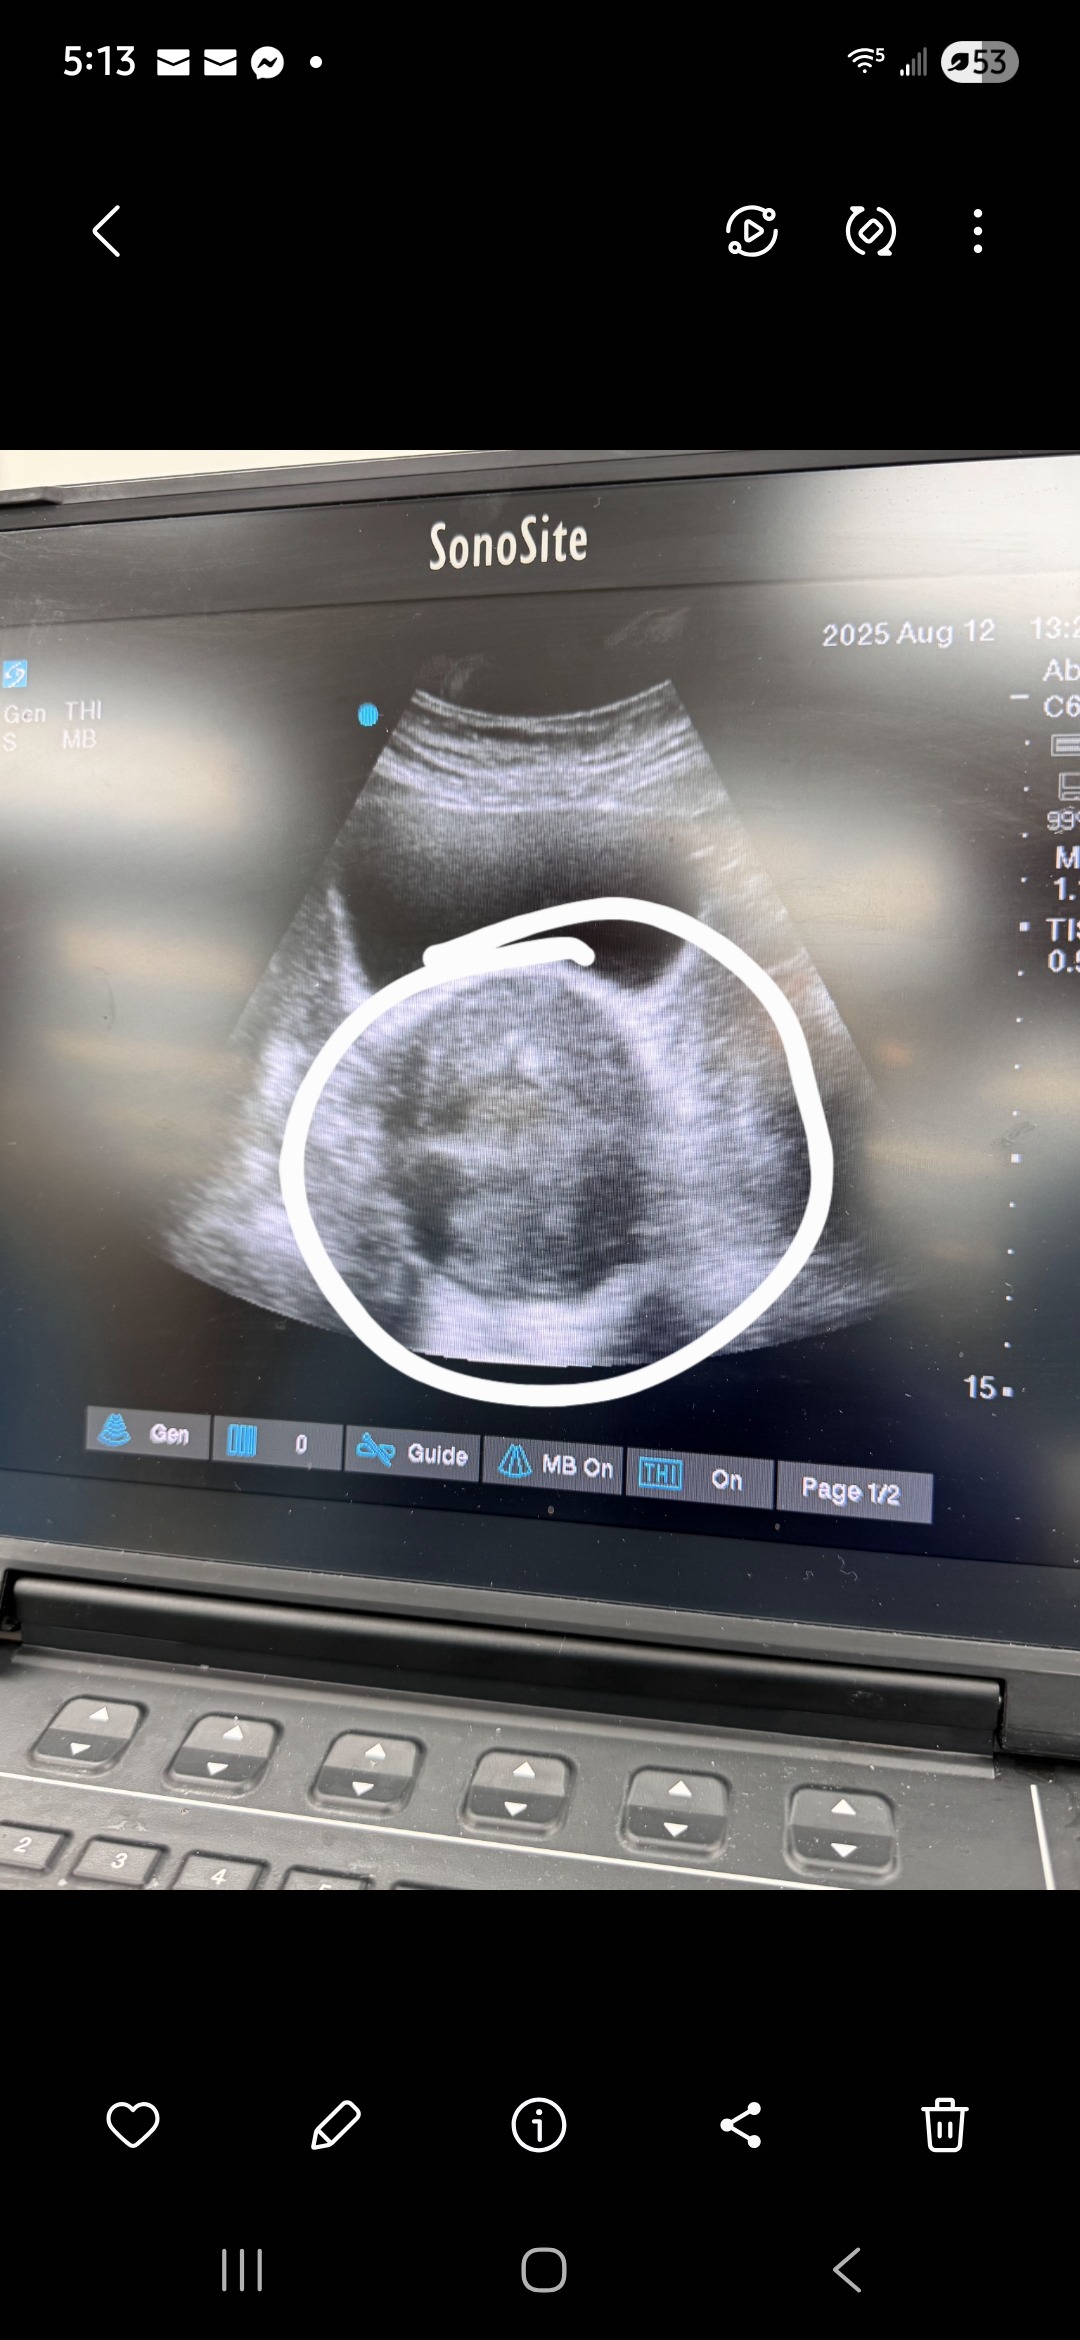

Brittany Cox has dedicated her life to helping others as a paramedic, starting her career at Anson EMS right after graduating high school and continuing her EMS work in Abilene for the last 11 years. As a single mom to her 6-year-old daughter, she’s always put her family and her community first, working long hours and extra shifts to make sure everyone is cared for. Now, Brittany is facing a major challenge of her own. She’s scheduled for major stomach surgery to remove a large tumor at Hendricks in Abilene on August 13th and will need to take at least two months off work to recover.